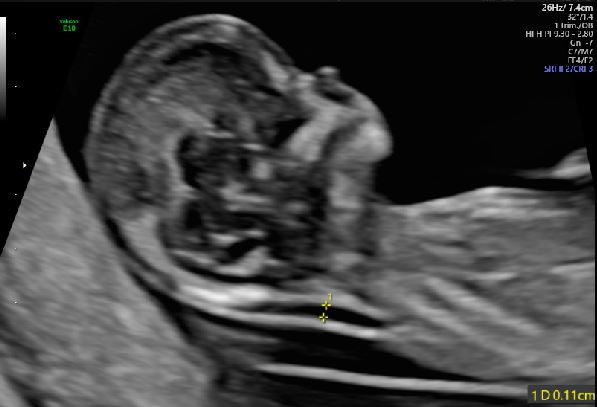

The NT is measured at a gestation age of 11w0d to 13w6d weeks with a corresponding CRL of between 45 mm and 84 mm. A mid-sagittal view is taken in a neutral position away from the amnion. The maximum translucency is obtained with the callipers “on-to-on” as illustrated. A certification program is available through: The Fetal Medicine Foundation.